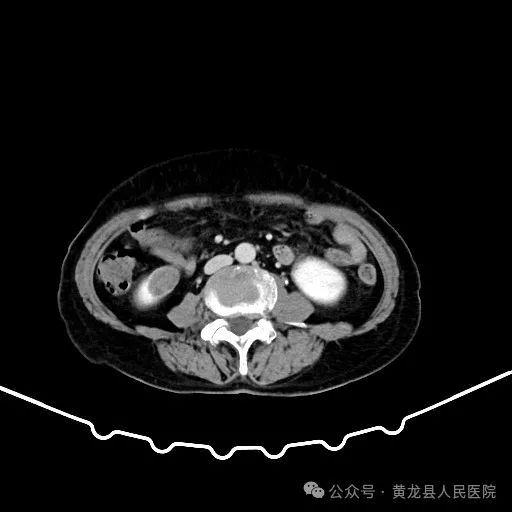

双肾增强CT

患者男性,70岁,因“发现右肾肿物1年余”收住于我院外科,经查体及相关检查后诊断为:右肾肿瘤。为尽早解除患者疾病困扰,方继荣主任迅速组织泌尿外科、手麻科、普外科等多学科进行会诊,对患者的病情进行了全面而深入的评估。最终确定详细周密手术方案,将患者病情及治疗方法告知患者及家属征得同意后,由我院泌尿外科刘涛主治医师实施手术。